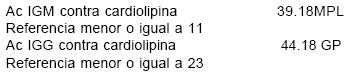

En la UC se solicita interconsulta al servicio de Hematología del HE quien solicitó pruebas de coagulación especial (PCE1), anticardiolipina (ACC) y anticoagulante lúpico (AL) (Cuadro I).

Con estos resultados se hizo el diagnóstico de síndrome antifosfolípido.

Los anticuerpos antifosfolípido son un grupo amplio y heterogéneo de inmunoglobulinas que incluye, entre otras, (AAC) y (AL).4,2,10–12 Los AAC pueden ser IgM o IgG, rara vez IgA. IgG se considera el más patogénico.2,10,11

• Anticuerpos anticardiolipina

– AAC IgG o IgM presentes en la sangre en moderados o altos niveles, en 2 o más ocasiones con seis semanas de separación.• Anticoagulante lúpico